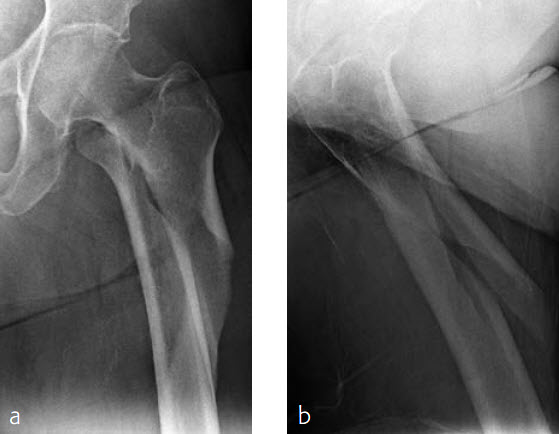

Case 1: Subtrochanteric femur fracture

An 86-year-old patient fell at home while dressing, sustaining a subtrochanteric left femur fracture (Fig 1). The CT scan confirmed no involvement of the intertrochanteric region or the piriformis fossa. Fixation was with FRNA for piriformis fossa entry point in reconstruction locking mode and transverse locking (Fig 2).